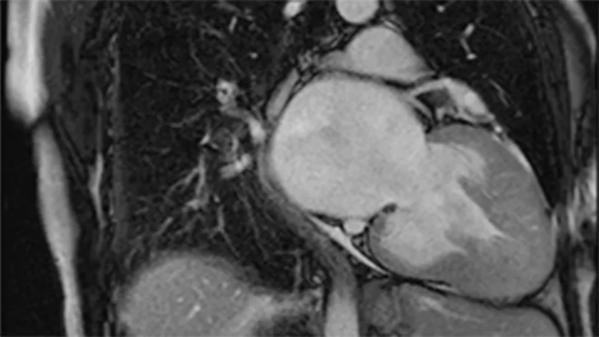

Imaging of non-obstructive hypertrophic cardiomyopathy